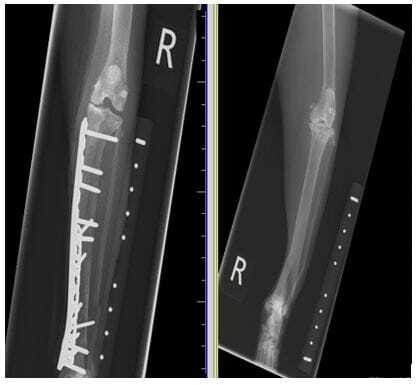

FIGURE (3) This fracture was repaired under compression, as you can see the two ends of the fracture are accurately aligned